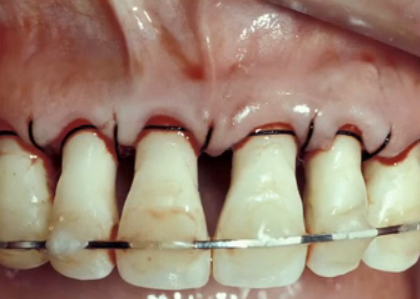

Papillae are very much like a coiled spring; when compressed, it will bounce back, and if it’s stretched, it goes back down. However, if we move papillae, it will regenerate back. How far back really depends on the patient, but the regeneration will re-create biologic width and produce a volume of tissue that’s coronal to the attachment. We can ultimately determine how tall the papillae will get by measuring the embrasure that balloon of fluid grows into.

Van-der-Velden-U conducted a study, Regeneration of the Interdental Soft Tissue Following Denudation Procedures, on posterior teeth to evaluate how much papillae regenerates on the average human. This study revealed that papillae consistently grow back at 4–4.5 mm above bone and develop a 2–2.5 mm sulcus depth.